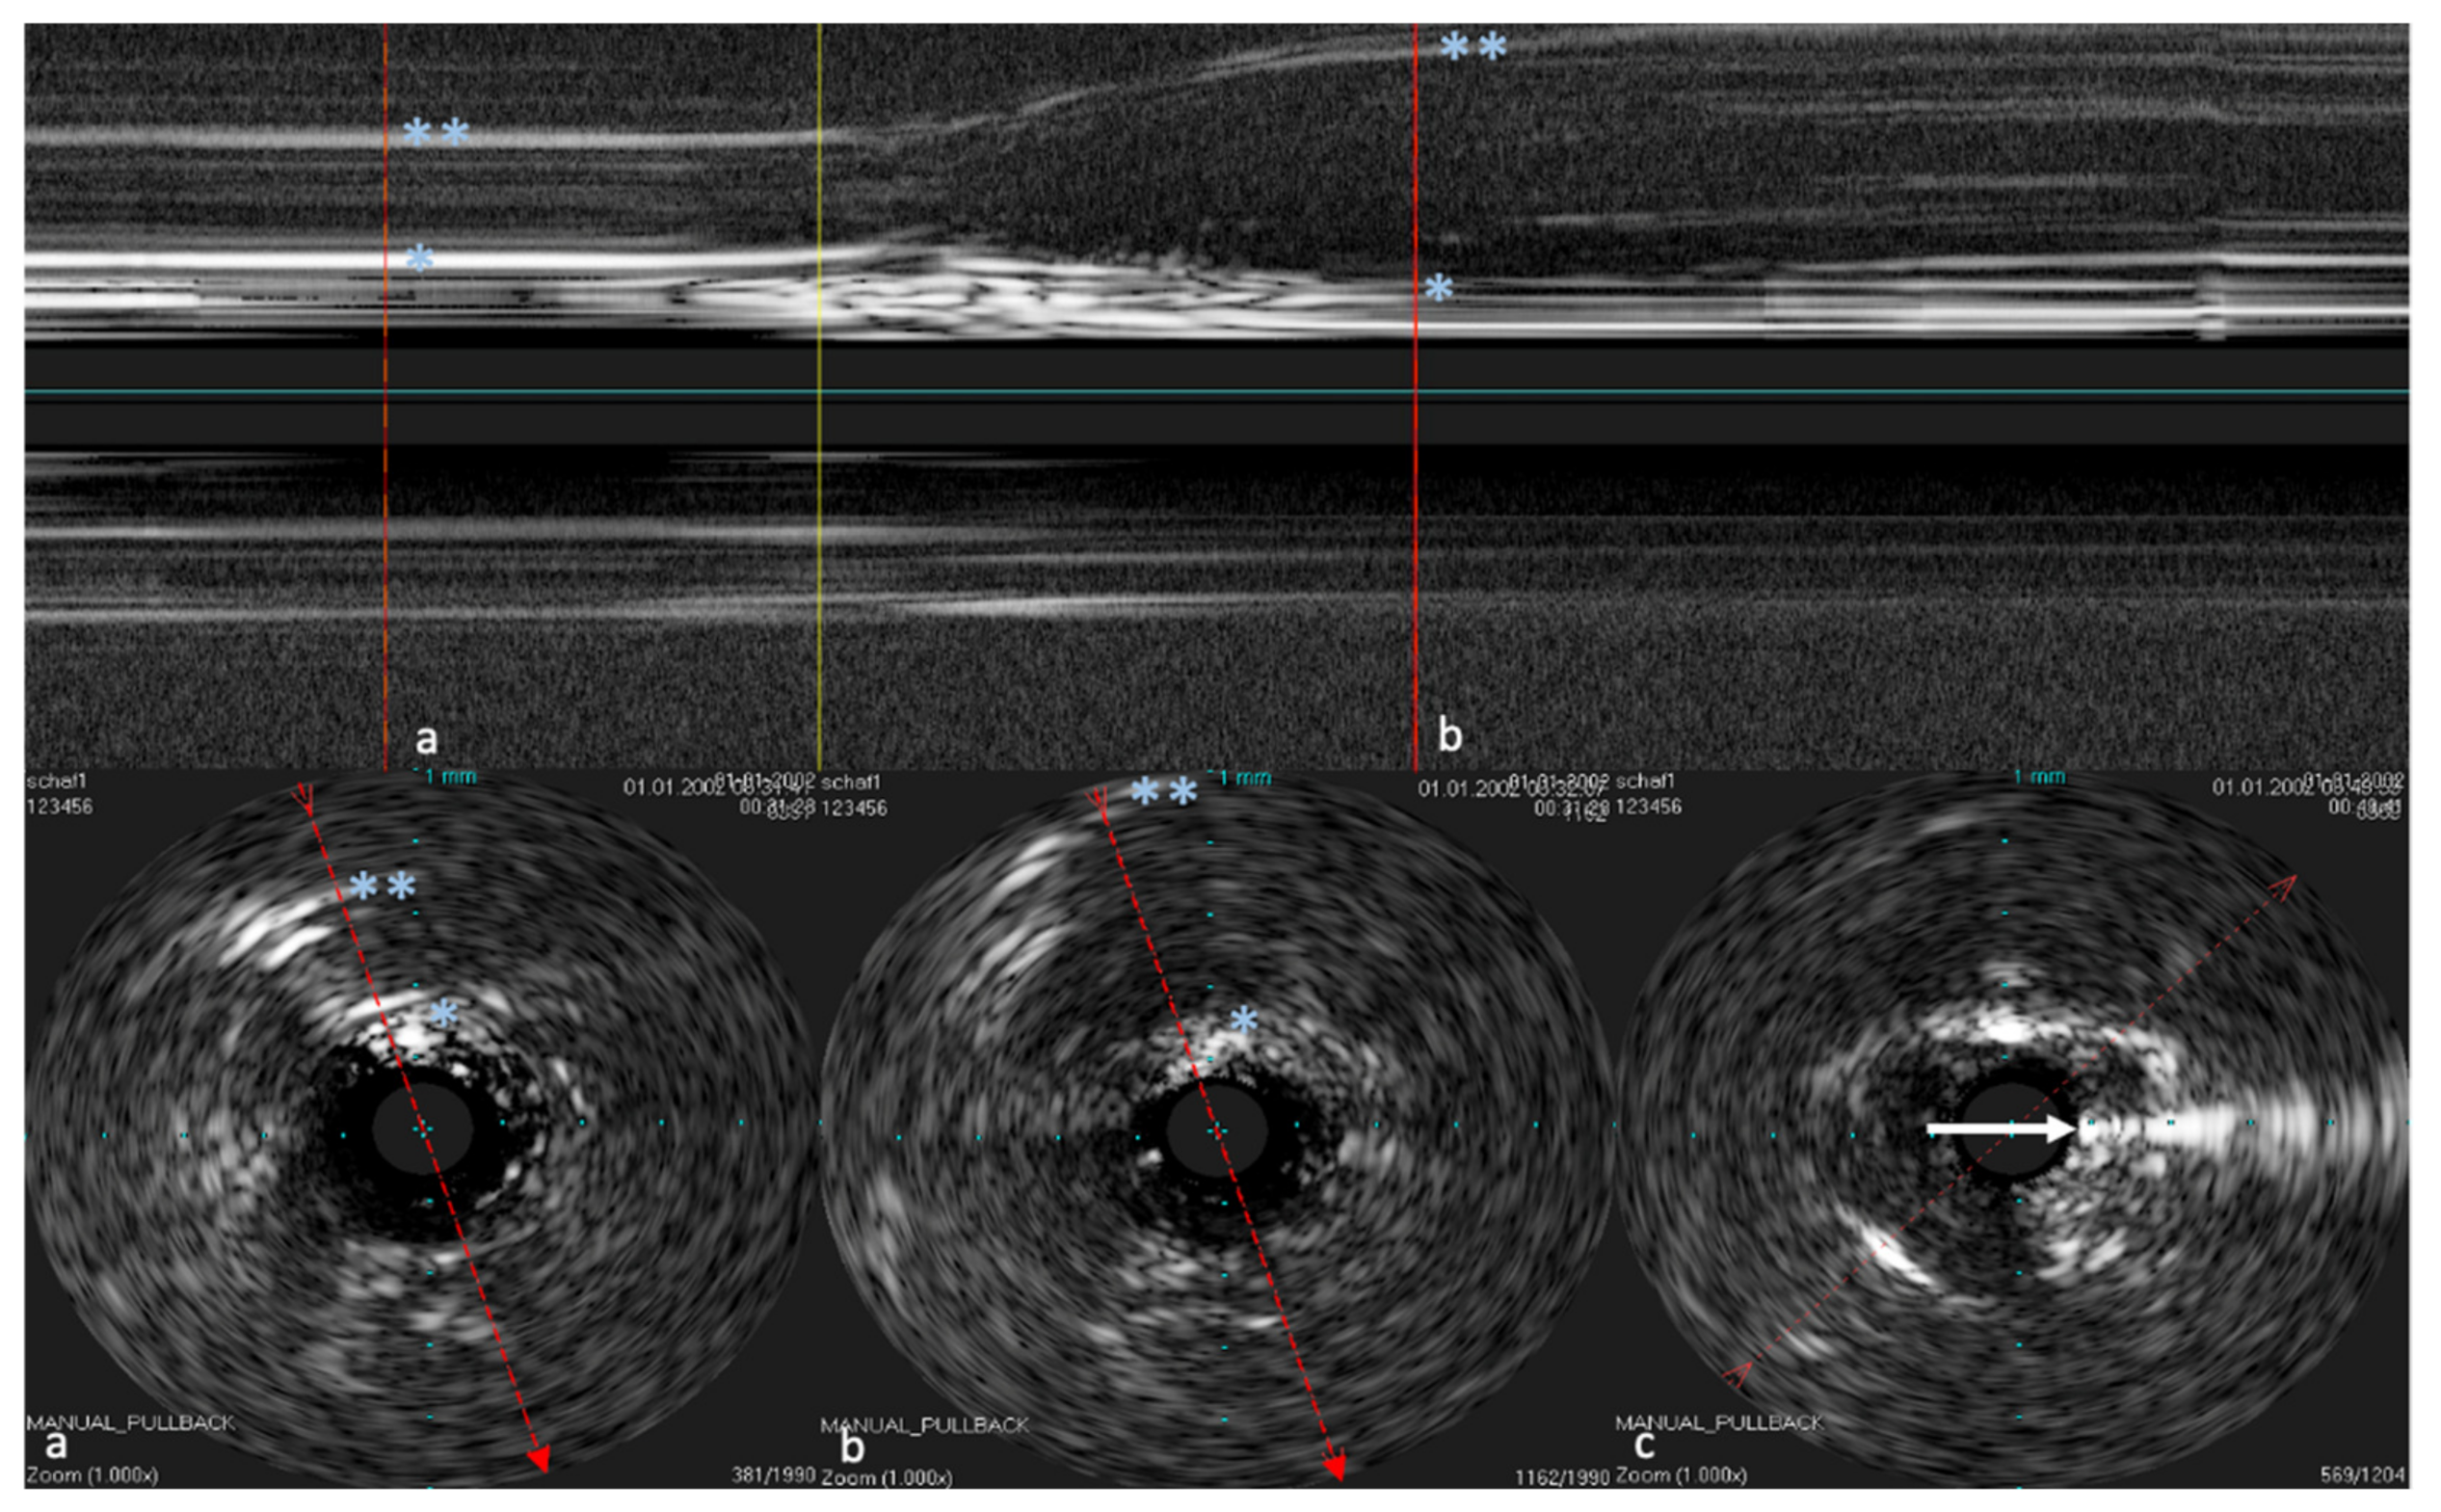

Deposition of HA next to the ET was observed using a stationary probe. With a stationary probe, the longitudinal view becomes a timeline. This allows us to observe how the HA is distributed in the tissue and how the depot expands (Figure 6).

Figure 6. Sonographic image of the injection of HA into the tissue. The probe remained stationary during this procedure. The upper image shows the temporal course of the procedure over approximately 20 s. Image (a) is the cross-section of the ET before the injection and image (b) during the injection. The yellow line marks the start time of the injection. During the course, how the echogenic tissue layers (marked by the * and **) pressed apart due to the injected echo-poor HA is visible. Image (c) shows the cannula (marked by the white arrow) in the sonographic image. Note that image (c) is not from the longitudinal view shown above.